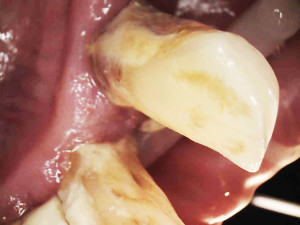

Postępowanie rozdzielono na dwie wizyty. Badaniem klinicznym, oceniając wskaźniki periodontologiczne, uzyskano wartości API 100%, PBI 100% świadczące o konieczności poprawy higieny i procesie zapalnym dziąseł, duże złogi kamienia nad i poddziąsłowego, bardzo obfity biofilm, pogłębione wszystkie kieszonki dziąsłowe, ciężkie zapalenie dziąseł, ruchomości zębów dolnych III stopnia, duży zanik kości. Badanie kliniczne błony śluzowej jamy ustnej nie wykazało zmian patologicznych.

Na pierwszej wizycie usunięto złogi kamienia nad- i poddziąsłowego za pomocą skalera ultradźwiękowego EMS oraz osady i biofilm za pomocą piaskarki airflow S2 EMS –użyto piasku AIR-Flow PLUS. Ponieważ pani jest bardzo wrażliwą osobą, a stan zapalny dziąseł był bardzo duży, pacjentka została miejscowo znieczulona do zabiegu.